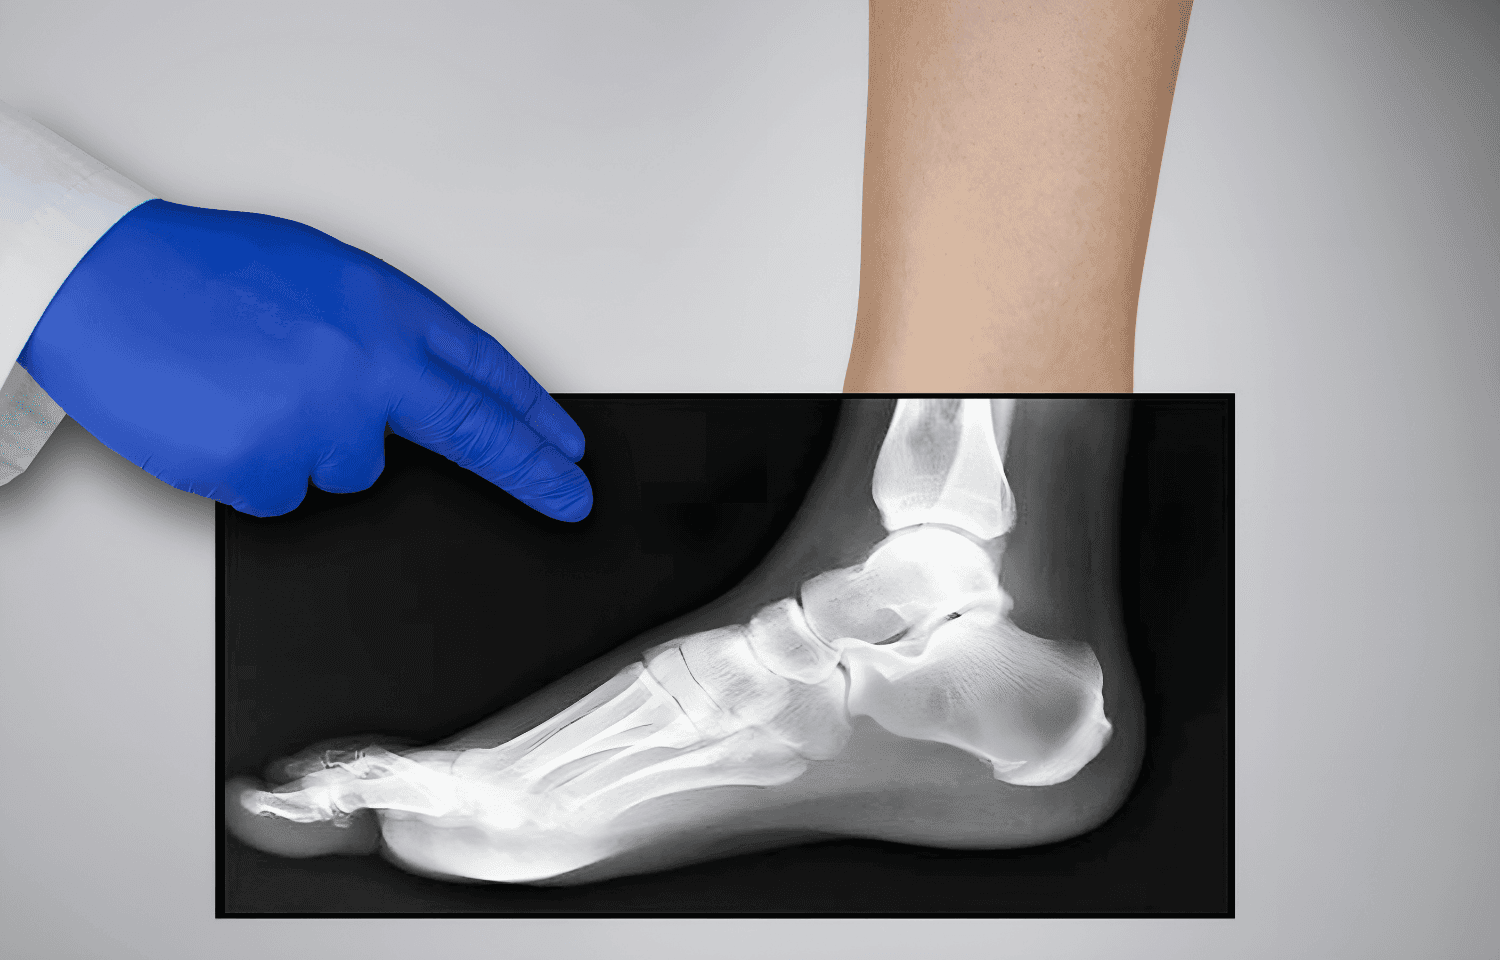

Röntgen görüntüleri, kemik ve eklem yapılarının detaylı incelenmesini sağlayarak bu süreçte kritik bir rol oynar. Röntgen, basit ve hızlı uygulanabilir bir görüntüleme yöntemi olarak birçok alanda değerlendirilir.

Röntgen Kullanım Alanları:

- Eklem sorunlarının tanımlanması

Röntgen görüntülerinin doğru okunması, tedavi planlamasında hataları en aza indirir ve uygun cerrahi veya konservatif tedavi yöntemlerinin belirlenmesini sağlar.